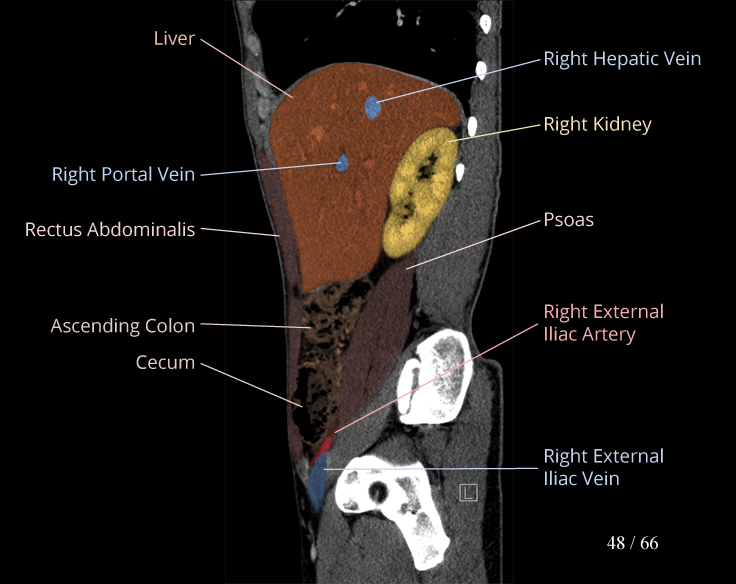

Body

Covers abdominal CT anatomy.